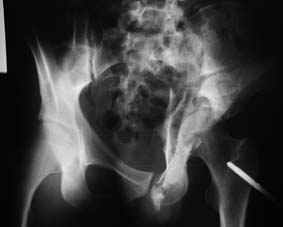

Все-таки надо бы начать не с КТ, а с обзорного снимка таза и косых проекций впадины.

Это обзорные и косые снимки